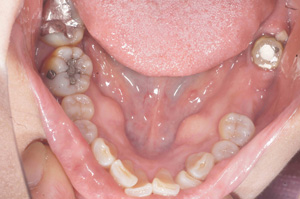

@@R.S‚³‚ñ@56Î —«  ‘åŠw‹³Žö @Žèp“ú@‚Q‚O‚O‚W”N ‚QŒŽ ‚X“úi“yj@㉺Š{  ƒm[ƒxƒ‹ƒKƒCƒhŽg—p@Ö¬“à’ÁÖ@•¹—p@@@

@@@@@ãŠ{  All on ‚U@‘¦Žž‰Ád@@

@@@@@@@@@@@@@ Rpl Tapered Rp  ‚P‚O mm(‚U–{)

@@@@@‰ºŠ{¶‰E@‘¦Žž‰Ád@ ‚R Unit Bridge@

@@@@@@@@@@@ @Rpl Tapered Rp  ‚P‚O mm(‚S–{)@@–ƒWƒ‹ƒRƒjƒAƒNƒ‰ƒEƒ“‚ÅÅI•â’Ô